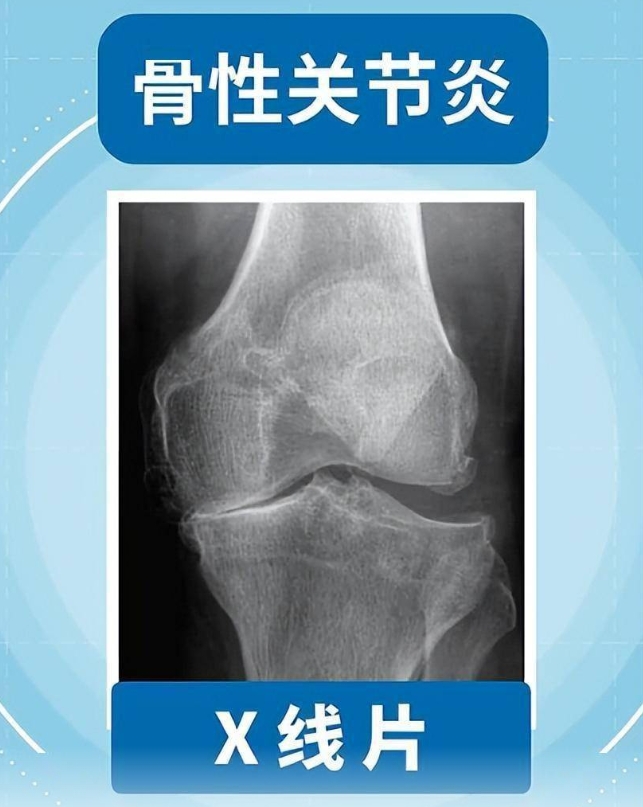

新浪微博网页版:且行且珍“膝”!膝盖脆弱的你,请收好这份护“膝”秘籍